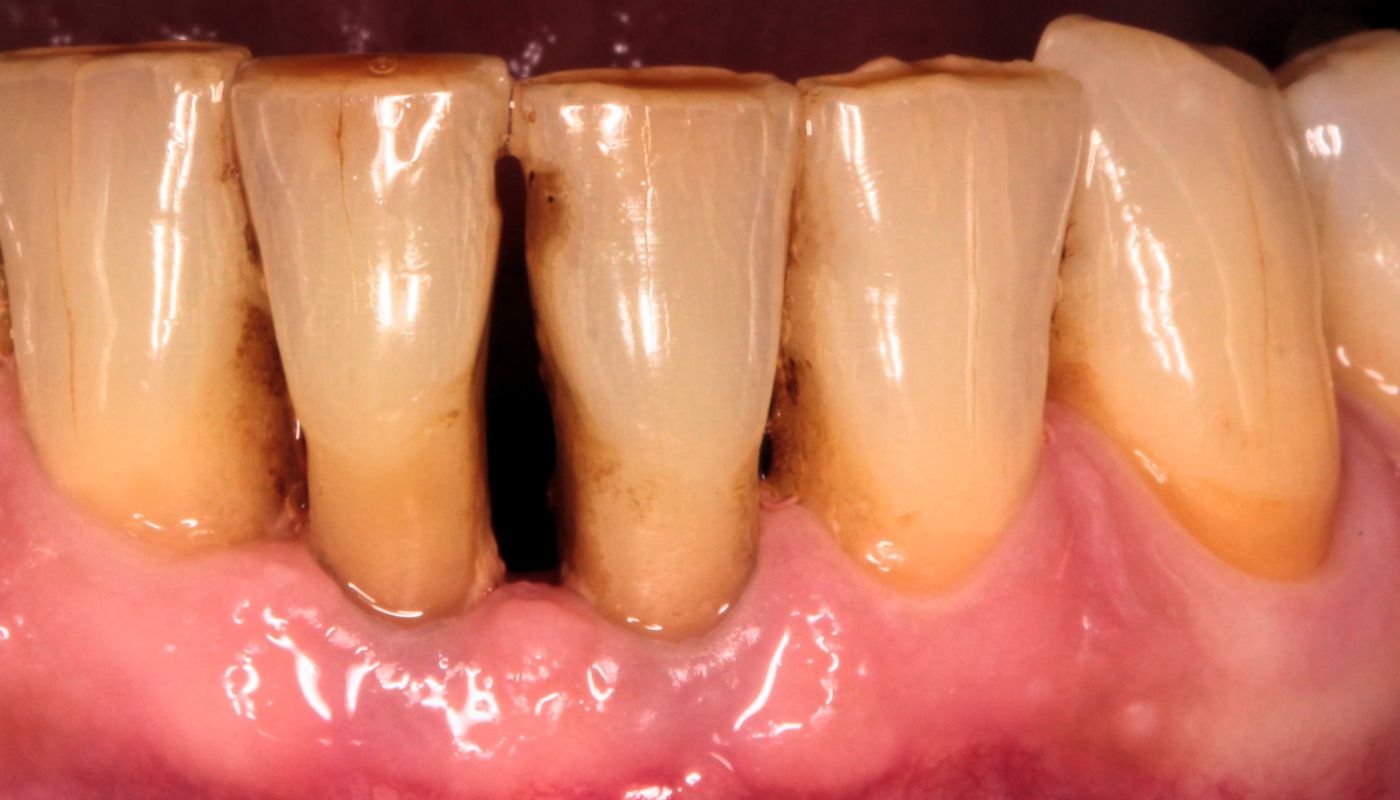

Odsłonięcie szyjek zębowych, gdzie pojawia się stan zapalny, spowodowane jest nagromadzeniem się płytki bakteryjnej, która doprowadza do powstawania kamienia nazębnego. Nieleczona wiele lat choroba przyzębia, zwana paradontozą (z łac.periodontitis) powoduje trwałe zanikanie dziąseł i kości, a w konsekwencji odsłonięte szyjki oraz powierzchnie korzeni.

Niewłaściwa higiena zębów czy palenie papierosów stwarzają idealne warunki narastania płytki nazębnej na powierzchni zębów. Zalegające złogi nazębne stykając się z dziąsłami powodują ich drażnienie, przez co stwarzają podłoże do wytwarzania stanu zapalnego przyzębia. Dochodzi do obniżania się nasady zęba oraz odsłaniania szyjek zębowych.

Odsłonięte szyjki zębowe narażone są większą adhezję (przyleganie) płytki nazębnej oraz osadzanie się kamienia. Dodatkowo, w wyniku niekorzystnej akumulacji płytki bakteryjnej oraz różnicy grubości szkliwa przy szyjce zęba w stosunku do korony, dochodzi bardzo często do zmian próchnicowych. Leczenie próchnicy w przypadku odsłoniętych szyjek jest obarczone dodatkowym ryzykiem powikłań (np. konieczność leczeni kanałowego). Wynika to z lokalizacji oraz bliskości miazgi.